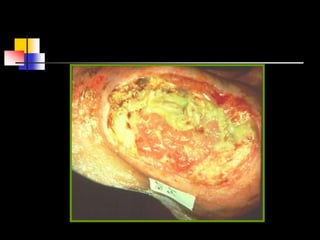

PrPresure Ulcer Stagingessure Ulcer

Staging skin loss

Full thickness      Stage III

involving damage to, or

necrosis of, subcutaneous

tissue that may extend down

to, but not through,

underlying fascia. The ulcer

presents clinically as a deep

crater with or without

undermining of adjacent

tissue.